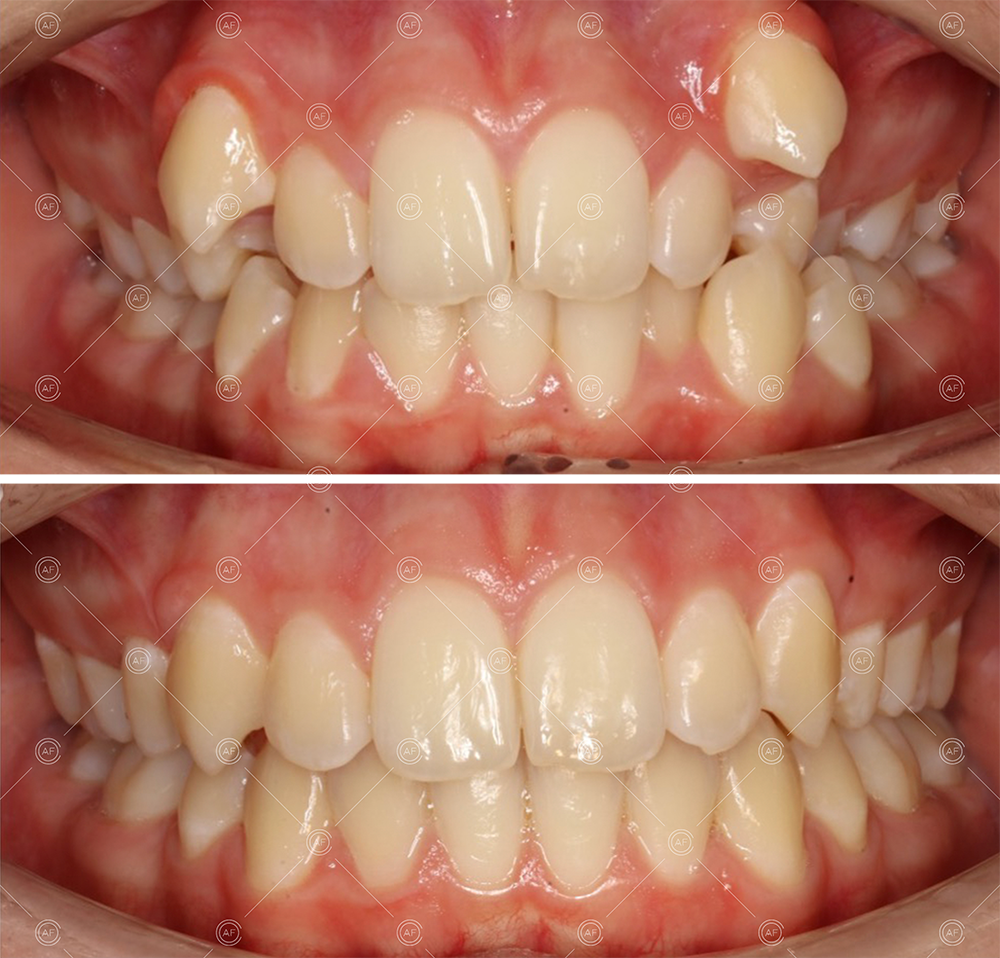

This patient (MH) began her active orthodontic treatment in October 2019 at almost 13 years old. She was unhappy with the appearance of her upper and lower teeth, and especially concerned about the unsightly nature of the high and buccally positioned upper left canine.

about this case…MH presented with class 1 incisors on the class 1 skeletal base with a slightly increased vertical proportion. She had severe crowding in the upper arch and moderate crowding in the lower. Due to the crowding in the lower arch, the lower centre line was off to the left by 2mm.

Buccal segments were essentially class 1 on the right hand side and a full unit class 2 on the left. This is due to buccal exclusion of the upper left 3 and mesial drift of the upper buccal segment.